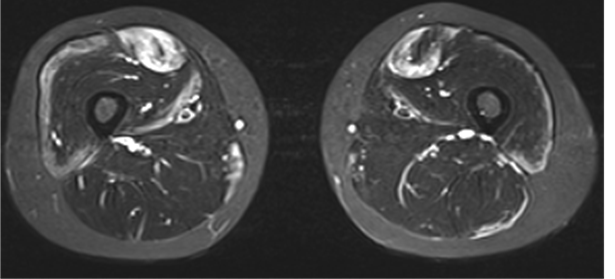

診察(徒手筋力テスト)で全身の筋力の強さを調べ、筋炎の重症度を評価します。血液検査では、筋肉に関連した酵素(筋原性酵素:クレアチニンキナーゼ[CK]、アルドラーゼなど)の数値を調べます。また、筋肉に細い針を刺して筋肉の状態を調べる筋電図や、場合によってMRIで筋肉の中の炎症部位や広がりを評価します(図4)。

図4. 筋MRI(太腿部の断面像:白い箇所が筋肉内の炎症を示唆する所見)